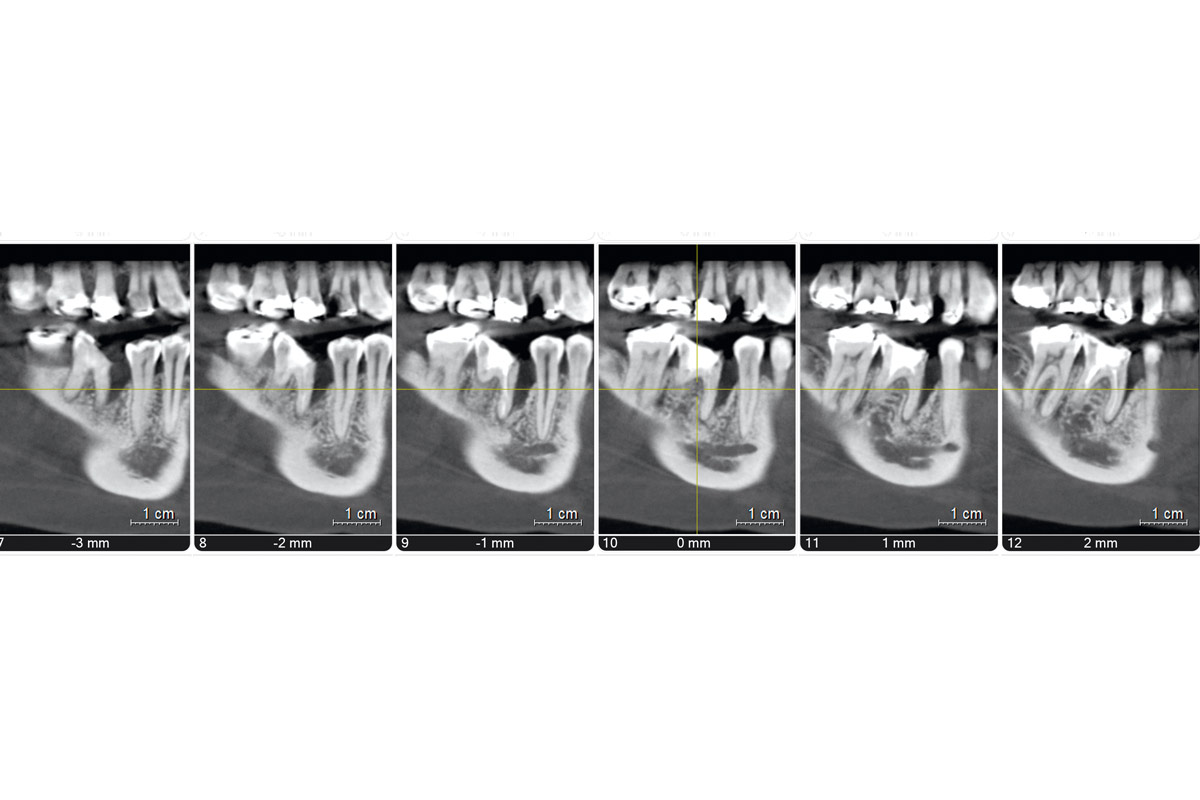

2/19 - CBCT Tooth 4.6

Immediate implant placement using maxresorb® - Dr. Alejandro Signorio

3/19 - CBCT tooth 4.6